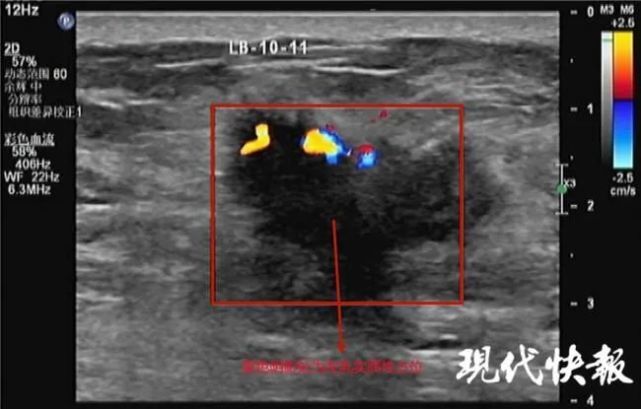

曹明华为老人做了体格检查,发现老人的左侧乳房有鸭蛋大小,触诊可及明显腺体感。进一步 B 超检查显示:左侧乳房发育,范围约 5*5cm,双侧腋窝见淋巴结,考虑乳腺增生。因增生腺体较厚,已无法自行消退,两侧乳房不对称影响美观,老人要求手术切除增生腺体。